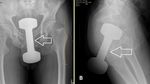

Pria 68 tahun mengaku rutin menggunakan kaleng hairspray untuk melancarkan BAB, tapi kali ini tersangkut di dalam rektum. Dokter berhasil mengeluarkannya tanpa komplikasi serius. (Foto: Malaysia Family Physician)

Pria 22 tahun datang ke IGD dengan gelas logam tersangkut di rektum. Pasien akhirnya dioperasi dengan membuka rektum dan membuat kolostomi sementara, lalu pasien dipulangkan dengan pemantauan psikologis. (Foto: International Surgery Journal)